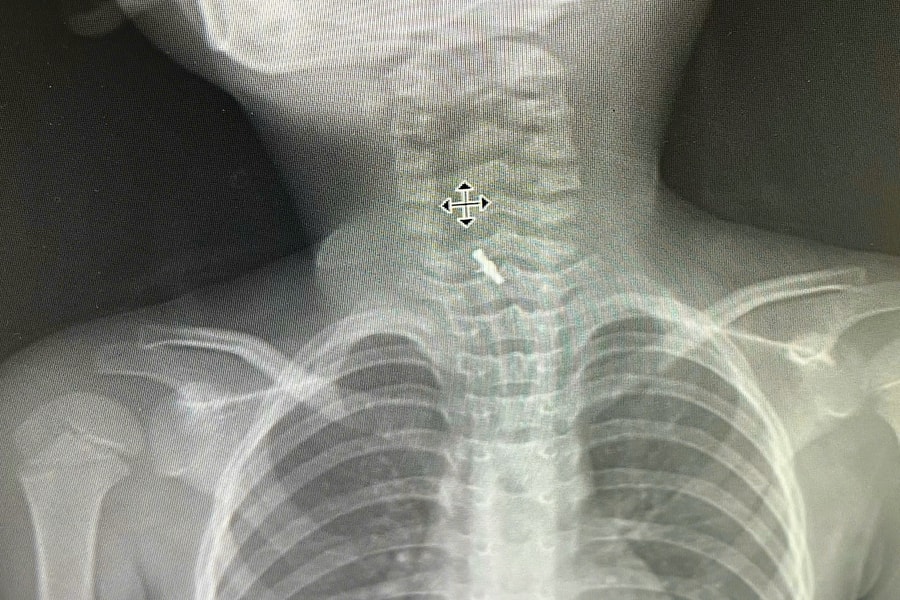

Bé 5 tuổi ở Phú Thọ phải đi cấp cứu vì nuốt kẹp tóc

Một bé gái 5 tuổi ở Phú Thọ vô tình nuốt kẹp tóc khi chơi ở lớp, dị vật mắc trong thực quản may mắn được bác sĩ nội soi lấy ra an toàn.